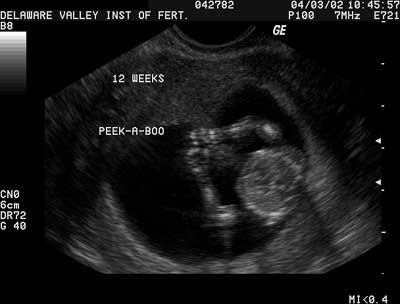

2. At 11 weeks,

6 days, it's very common to observe the fetal hands around the fetal face, sometimes

covering the face or placing a finger in the mouth.